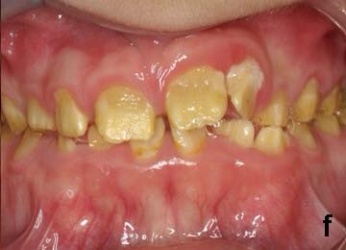

٢- سوء تشكل طبقة العاج (Dentinogenesis Imperfecta).

النوع الثاني وهو سوء تشكل طبقة العاج Dentinogenesis Imperfecta قد يكون مصاحبا لمرض أكثر خطورة وهو سوء تشكل العظام (Osteogenesis Imperfecta) ويصيب كلا من الأسنان اللبنية والدائمة بسبب التحول الجيني المصاحب.

وهو أصعب من ناحية العلاج لأن الطبقة المصابة هي الطبقة الداخلية للسن والتي تعتبر الجسم الداخلي لتركيبة السن لذا فالأسنان تكون ضعيفة سهلة الكسر و...يميل لونها إلى الرمادي الداكن أو البني المصفر.

ومن طرق العلاج المعروفة تلبيس الأسنان بتيجان مصنعة من الزيركون، خاصة الخلفية منها وذلك للحفاظ على علاقة الفكين ببعضهما التي قد تتأثر بسبب تآكل تيجان الضروس.

كما أن استخدام الحشوات في مثل هذه الحالات صعب لأن طبقة المينا تكون هشة جدا. وفي الحالات المتقدمة يتم عمل طقم كامل للأسنان فوق جذور الأسنان المتبقية (Overdenture).